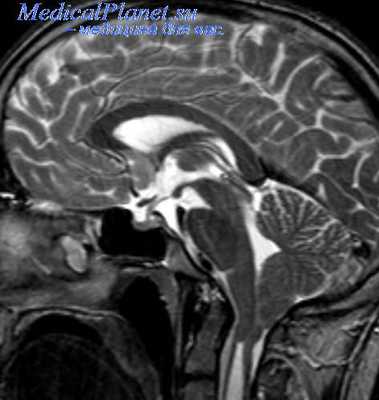

- МРТ для исключения патологического процесса в стволе мозга или мостомозжечковом углу

МРТ головного мозга особенно показана при подозрении на поражение ствола головного мозга или основания мозга (например, невринома кохлео-вестибулярного нерва).Компьютерная томография по своей диагностической ценности превосходит МРТ при визуализации переломов основания черепа. Исследование спинномозговой жидкости показано при симптомах, свидетельствующих о возможности менингита, энцефалита, васкулита и других заболеваний.